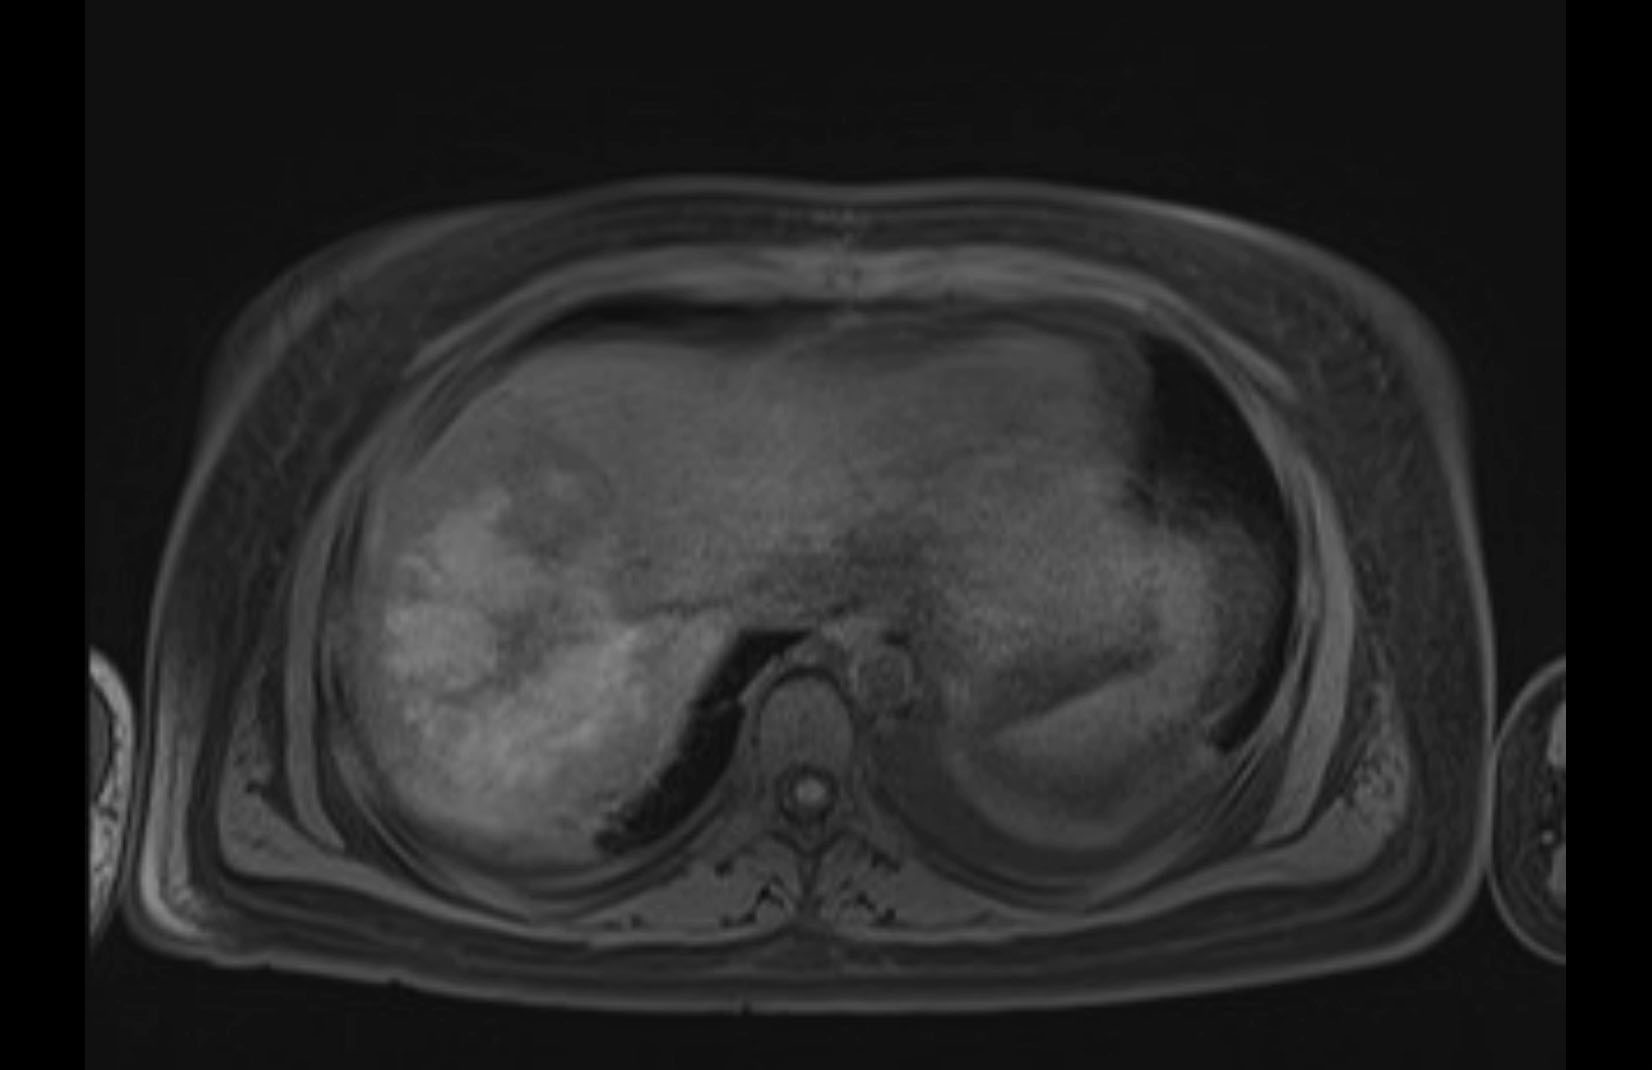

MRI T1

Imaging analysis

Based on initial findings, which issue(s) would you be most concerned about?